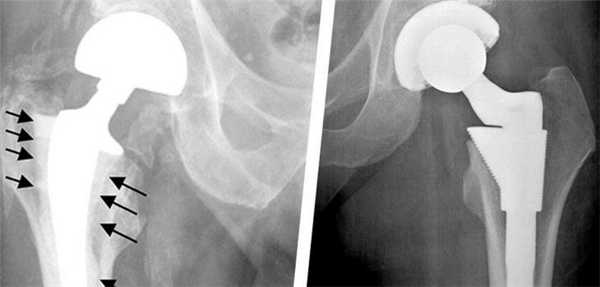

Признаки расшатывания эндопротеза тазобедренного сустава: как определить?

Методика доказала на практике свою эффективность, однако, даже самые совершенные технологии могут в долгой перспективе привести к возникновению осложнений. Нестабильность частей эндопротеза - самая часто встречающаяся патология, которая может вызвать нежелательные последствия и привести к необходимости повторной операции.

Все дело в том, что установленный имплантат влияет на движения тазобедренного сустава, как при тотальном эндопротезировании, таки при замене лишь части поврежденного сустава. В результате процесс восстановления костной ткани может замедлиться. Расшатывание ножки протеза в большинстве случаев приводит к развитию местного остеопороза. Таким образом, ограничивается подвижность самого эндопротеза.

К сожалению, современные научные и лабораторные исследования не смогли определить материал для протезов, которые бы не наносил абсолютно никакого вреда здоровью человека. В результате трения компонентов имплантата друг о друга мельчайшие частицы оседают в окружающих тканях, вызывая инфекционные процессы и отмирание тканей. Также может нарушится локальное кровообращение. Поэтому при появлении первых признаков расшатывания эндопротеза тазобедренного сустава следует немедленно обратиться за помощью к лечащему врачу.

Смещение протеза

В результате данного явления вживленный имплантат не только теряет фиксацию и расшатывается, но и приводит к постепенному или резкому изменению длины ног. В таком случае требуется немедленная консультация у врача и повторная операция на конечности. К основным причинам можно отнести следующие:

Остеолиз

К образованию данного процесса может привести частичное или полное разрушение кости, которое наступает в результате взаимодействия компонентов протеза с живой тканью.

Перелом эндопротеза

Диагностика переломов протеза, которые периодически случаются, дает основания предположить следующие причины таких последствий. К ним относится:

- неправильный подбор индивидуального имплантата;

- чрезмерная или преждевременная высокая физическая активность пациента; пациента.

К особым случаям относится расшатывание и повреждение отдельных компонентов протеза. В достаточно короткий срок может разрушится структура полиэтиленового вкладыша или бедренной ножки. Вывих или перелом эндопротеза также случается достаточно часто. Поэтому в обязательном порядке следует соблюдать рекомендации специалистов, а также осуществлять диагностические и профилактические мероприятия. Это гарантировано поможет предотвратить появление негативных последствий операции.